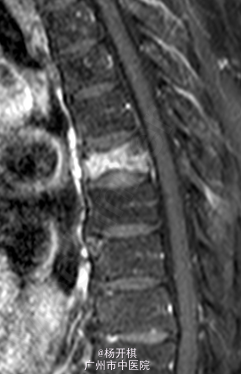

主诉:胸背部疼痛5天。 病史:老年男性,68岁。5天前在起床时突然出现胸背部剧烈疼痛,呼吸稍促,到急诊做心电图及BNP等排除心肌梗死,胸部X线示:T7压缩性骨折。建议患者入院治疗,患者拒绝,回家服药治疗。今日再次门诊就诊,疼痛严重,影响睡眠,影响活动等。患者一般情况较差。

查体:脊柱生理弯曲存在,无明显侧后凸畸形。胸12、腰1-3棘突、棘间及棘旁压痛、叩击痛,余腰、骶棘间及棘旁无明显压痛或击痛。双侧坐骨神经出口处无压痛。四肢肌张力正常,四肢感觉、肌力无明显异常。双侧膝反射及踝反射正常,双侧踝阵挛阴性。双侧Babinski 征及Oppenheim 征(-)。双侧直腿抬高试验(-),加强(-)。 辅助检查:三大常规、血生化、肝肾功能均未见明显异常。患者胸椎动力位片正常,其余重要胸椎影像学如下。

诊断:胸椎压缩性骨折(T7)。 处理:患者入院后完善相关检查,并给予对症治疗,科里术前讨论决定:拟行手术:T7经皮椎体成形术。

讨论:患者发生与老龄化有关的椎体压缩性骨折,并引起持续性腰背痛;25%的月经后女性发生椎体骨质疏松压缩性骨折,其中大部分伴有不同程度的胸腰椎椎体骨折,所以对于骨科的患者,有风险的患者,建议防治骨质疏松,减少发生骨折的几率。